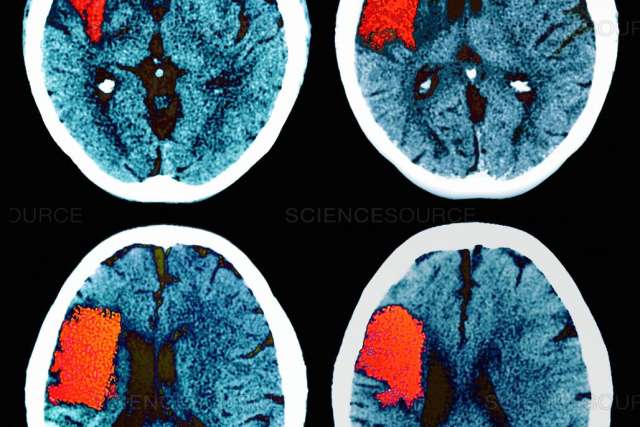

Brain scan

Stroke and dementia are two of the most common neurological disorders, and increasingly researchers are recognizing the link between the conditions.

Stroke, which is the leading cause of serious long-term disability, occurs when blood supply to the brain is blocked or a blood vessel bursts. A stroke greatly increases a person’s risk of developing dementia.